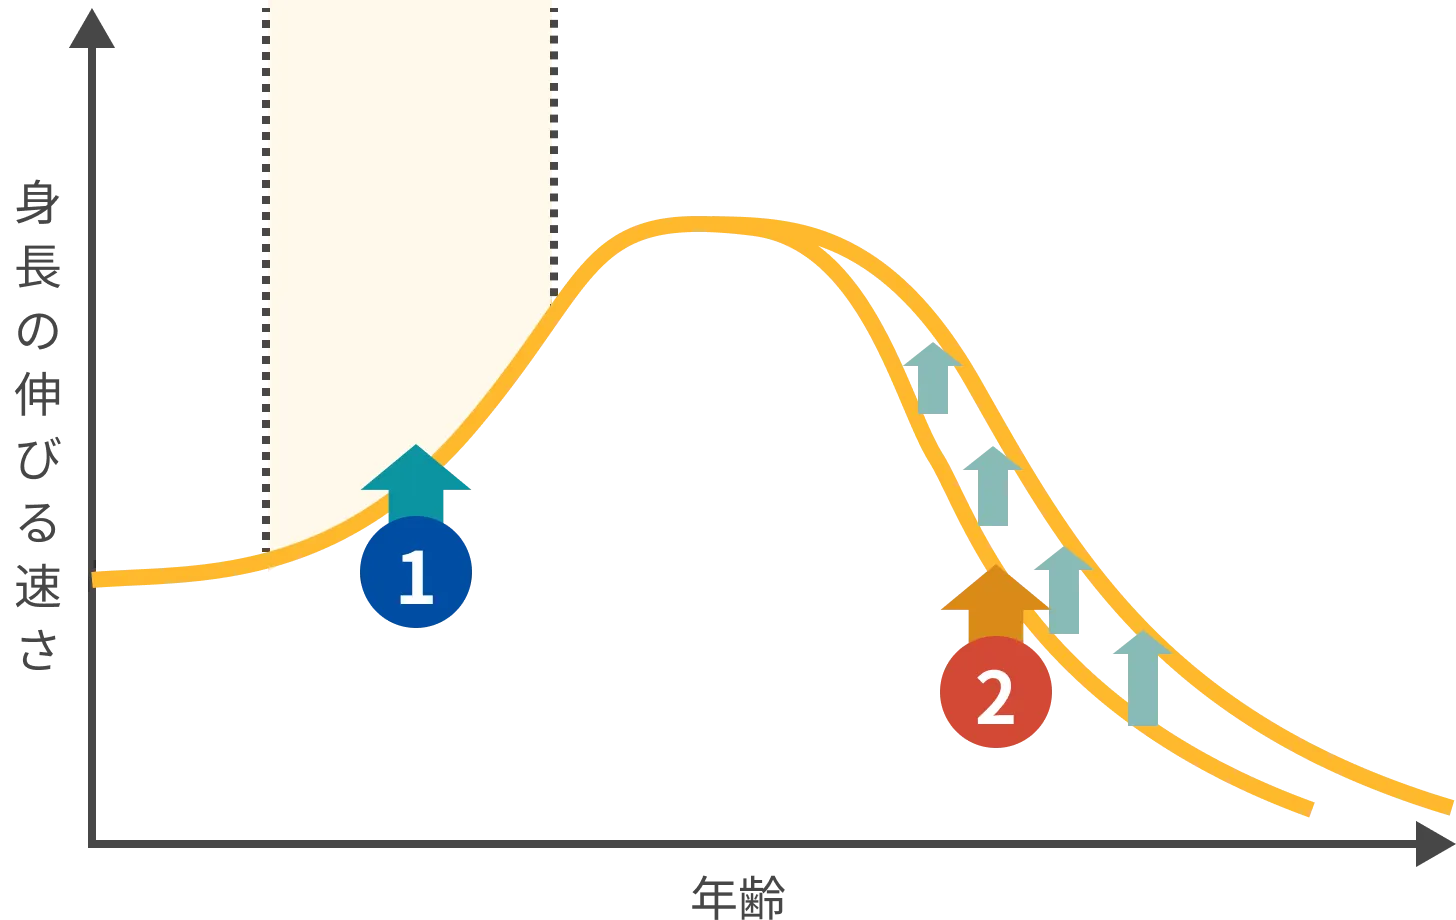

身長が伸びる期間の長さにも個人差があります。

思春期コントロール治療をすることで、身長が伸びる期間を伸ばすことができます。

ホルモンの働きを調整することで、思春期の進行を緩やかにして、身長が伸びる期間を長く保てるようにします。